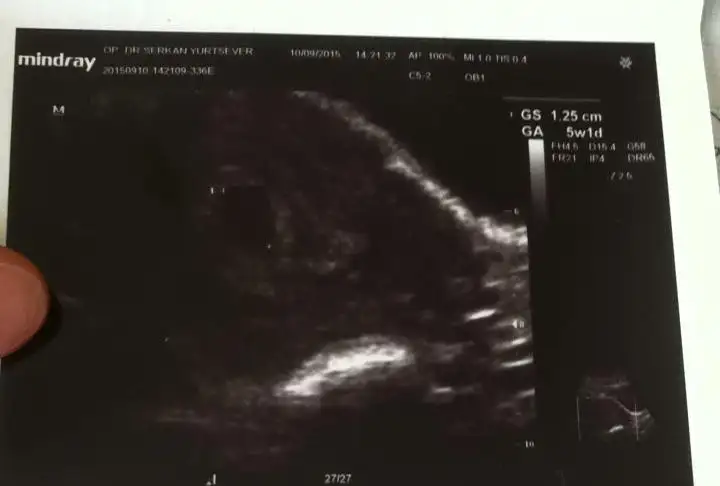

AMIN CANIM HEPIMIZIN KORKUSU BU SANIRIM RABBIM INS HIC BIRIMIZE GOSTERMEZ YASATMAZ BU ACIYIaynı durum ve korku bende de var 5+1 kese var hatta kesem 4 haftalıkken göründü 4 mm di dün 12 mm olmuş ama bebiş yok henüz daha erken dedi doktor ama insan endişeniyor işte boş gebelik korkusu bende de cokAllah ım inş. öyle bişi olmaz sağlıklı sıhhatli kalp atışlarını duyar sonrada kucagımıza alırız bebişlerimizi

doktor mu 7+2 diyor canım.. peki alttan ultrasyonla bakıldımı? sadece karından mı bakıldı ?çok sağol inşallah geçer. benim 7+2 hamile diyor kese en son bu salı gittim 1.77 cm o boş gebelik lafını duydum ya kaç haftalık ne zaman doğum olur hiç bir şey sormadım güya kalp atışını duyacaktım.